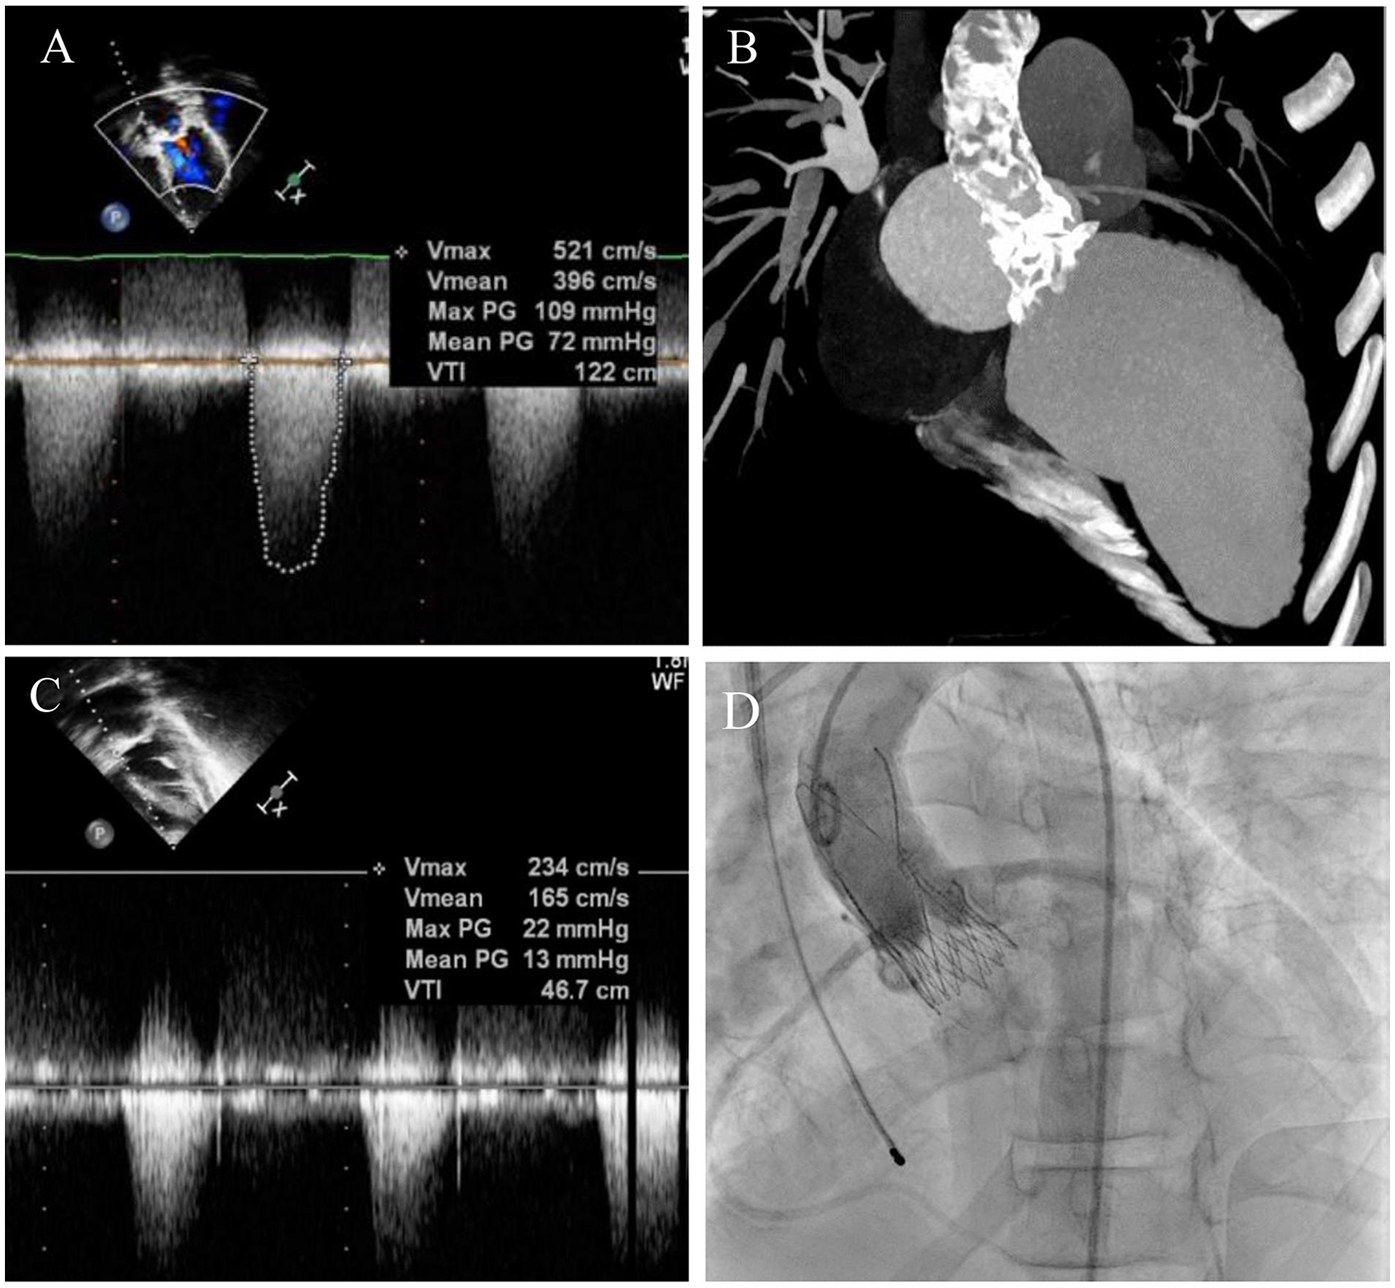

The patient was then admitted with New York Heart Association (NYHA) Class IV heart failure. A cardiac echocardiogram revealed enlargement of the left heart chambers [left ventricular (LV) end-diastolic dimension (EDD) 53 mm, z-score of 1.92; LV end-diastolic volume (EDV) of 116.6 ml/m2], decreased myocardial contractility of the left [left ventricular ejection fraction (LVEF) of 20%–22% using Simpson’s method] and right ventricles [tricuspid annular plane systolic excursion (TAPSE) of 9 mm], critical mixed aortic valve disease [aortic valve area (AVA) of 0.8 cm2, peak AV gradient of 109 mmHg, mean AV gradient of 72 mmHg, maximum velocity (Vmax) of 5.2 m/s, aortic regurgitation of 2°–3°, and vena contracta of 5–8 mm], moderate mixed mitral valve disease (Vmax of 1.64 m/s, mean MV gradient of 10 mmHg, and moderate mitral regurgitation), and pericardial effusion of 13–14 mm with no evidence of collapse (Figure 1A). In addition, left ventricular hypertrophy with posterior wall (13 mm, z-score of 4.98) and septum (19 mm, z-score of 5.51) thickening was diagnosed.

Figure 1

Pre-TAVI assessment and postprocedural result. (A) Preoperative echocardiography showing Vmax of 5.2 m/s and mean aortic pressure gradient of 72 mmHg. (B) CT-angiography demonstrating severe calcification of the aortic root and ascending aorta. (C) Postoperative transthoracic echocardiography confirmed a decrease in Vmax and mean AV gradient. (D) Postimplantation aortogram.

Based on the assessment results and the ineffectiveness of conservative treatment, a surgical intervention with the Konno–Rastan procedure and MV replacement was considered as the first option. However, due to severe calcification of the left ventricular outflow tract (LVOT), aortic root, and ascending aorta revealed on multidetector computed tomography (MDCT) (Figure 1B); decreased severe biventricular heart failure; and the high risk of open surgery, transcatheter aortic valve replacement was considered the only treatment option. After collecting signed informed consent from the parents, the TAVI procedure was conducted.

The intervention was performed with no complications. An ACURATE neo S 23-mm transcatheter bioprosthesis (Boston Scientific, USA) was implanted in an aortic position through a 14 Fr iSleeve transfemoral sheath (Boston Scientific, USA). Control angiography showed minimal paraprosthetic regurgitation and no signs of coronary ostia obstruction (Figure 1C). The operative access was sutured using a transcutaneous technique with Proglide + Angioseal (Abbott, USA; Terumo, Japan).

The post-TAVI echocardiography showed a well-functioning aortic valve (mean gradient of 12 mmHg and Vmax of 2.1 m/s) with trivial paravalvular leakage and no pericardial effusion. The parameters of both ventricles demonstrated substantial improvement with LVEF increased to 30% and TAPSE to 21 mm (Figure 1D). The moderate mitral valve disease apparent before the procedure remained unchanged.